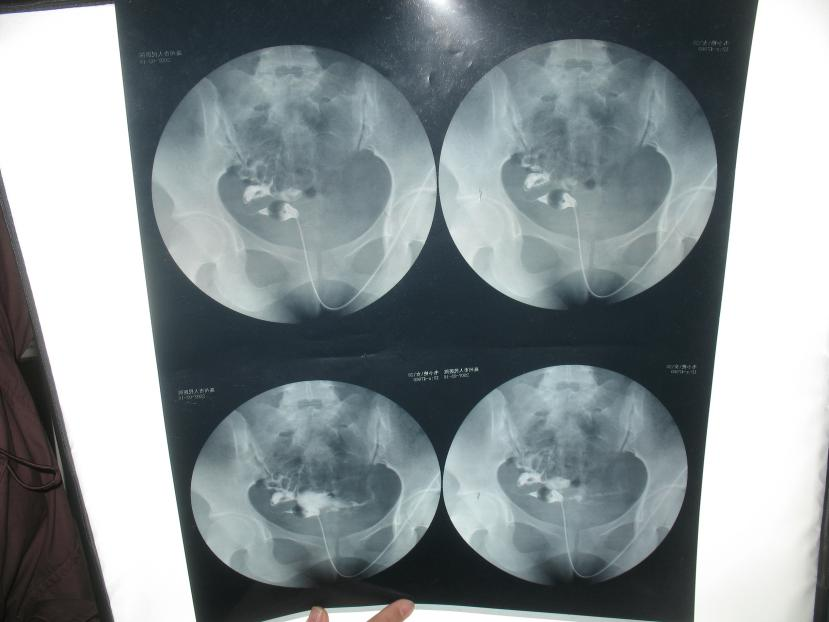

食用后:

治疗1个月后复查“白带支原体阴性”,第2月月经干净1天,行双输卵管通液,已经完全疏通。